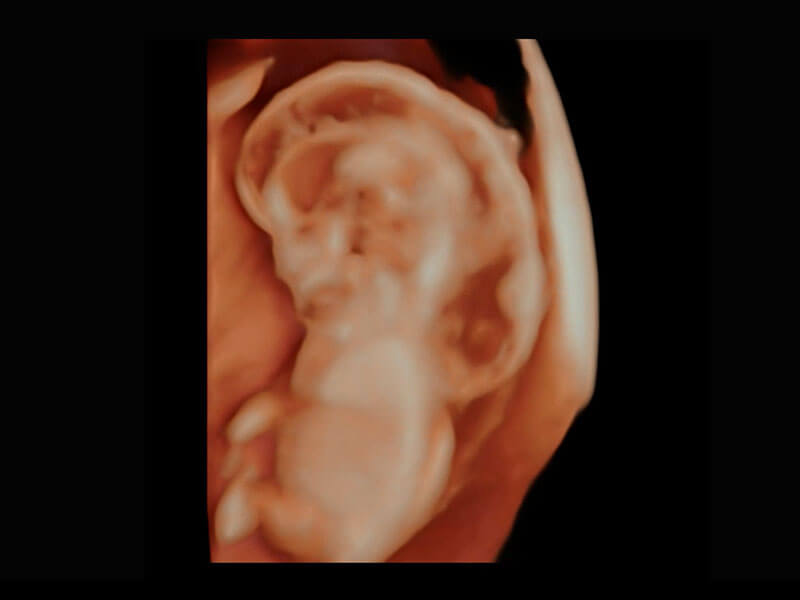

• 高分辨率容积成像-早孕胎儿

P60提供简单易学易用的高端诊断工具,为您中晚孕筛查提供快速清晰的解剖信息。